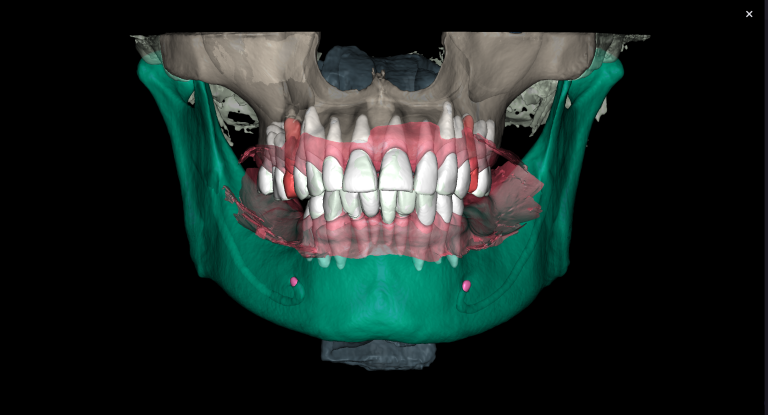

Diagnocat determined not only the presence, but also the localization of the focus of radiolucency of enamel and dentin, which was correctly indicated as “signs of caries” in the report

Please note that despite the fact that the radiolucent area is poorly visible when viewing CBCT, Diagnocat reflected in the report the presence of signs of caries and accurately indicated the localization